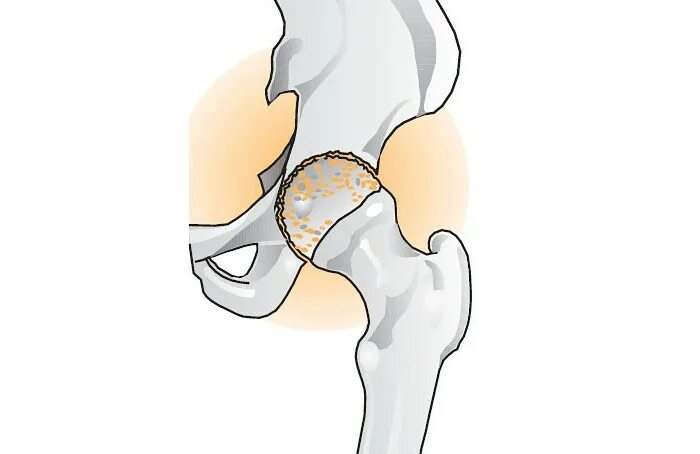

Коксартроз тазобедренного сустава 3